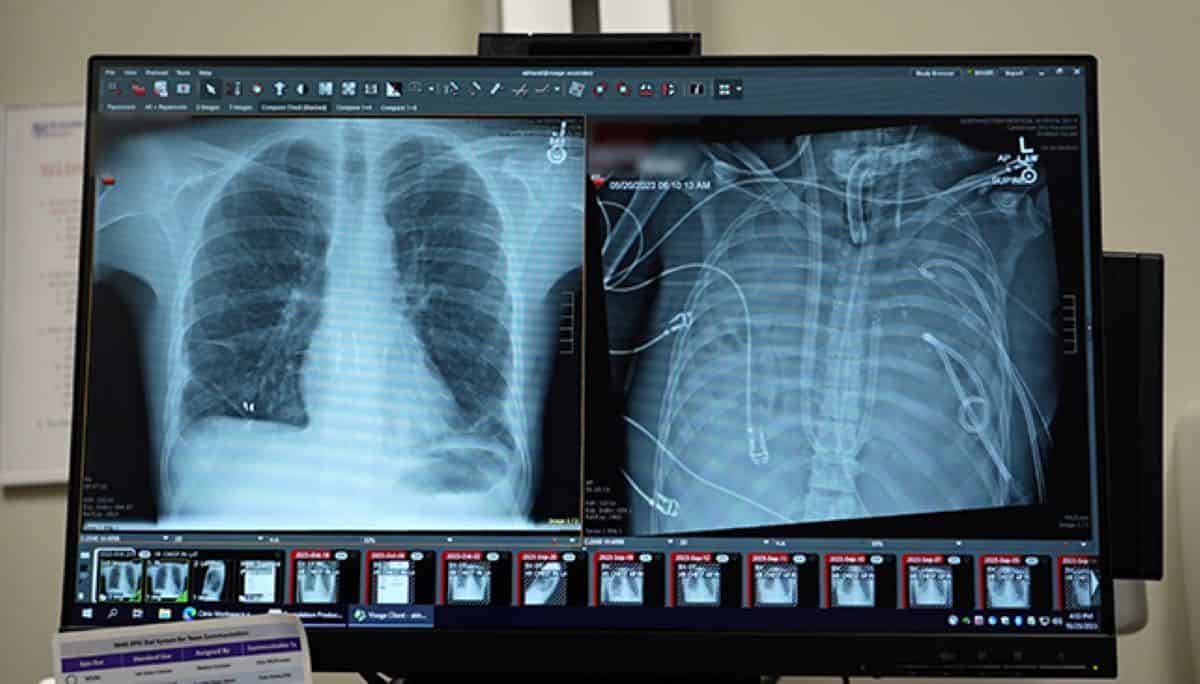

In the spring of 2023, a 33-year-old man arrived at Northwestern Memorial Hospital in Chicago with lungs that were rapidly shutting down. What started as a bout of influenza had spiraled into acute respiratory distress syndrome (ARDS). Then, a drug-resistant bacterial infection took hold.

Bharat and his colleagues decided to attempt something unprecedented. They performed a bilateral pneumonectomy—removing both lungs—and immediately connected the man to their custom-built artificial lung system.

The system worked by diverting blood from the right side of the heart, passing it through an oxygenator to scrub carbon dioxide and add oxygen, and then returning it to the left side of the heart. Crucially, the device balanced blood pressure so the heart could continue to beat normally.

Once the lungs were out, the doctors could finally examine the damage in detail. Using molecular and cellular analyses, the research team found evidence that the injury was irreversible.

The tissue showed widespread scarring and immune cell invasion. The cells that usually help regenerate lung tissue were largely absent. Instead, the lungs bore the molecular signatures of end-stage fibrotic disease.

For years, doctors have viewed ARDS as a condition from which lungs can recover if patients are supported long enough. This case offers biological evidence that, for some patients, recovery may never come.